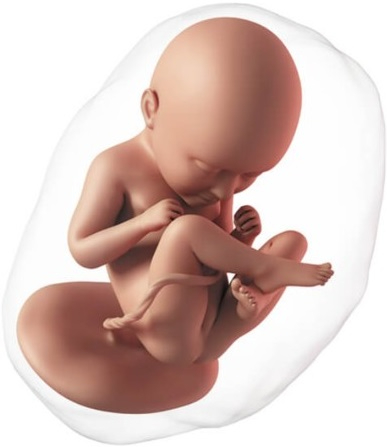

En esta semana inicia el segundo trimestre del embarazo. El feto mide aproximadamente 80 y 95 mm. El bebé crece rápidamente, los brazos alcanzan la proporción adecuada en relación al tamaño del cuerpo. La piel, que ya no es tan "transparente", se cubre aún más por vello denominado lanugo. Los músculos de la cara se desarrollan más, su sistema nervioso está más desarrollado, abre la boca en forma de bostezo, hasta se pueden meter los dedos en la boca. Al abrir la boca entra líquido amniótico, el cual pasa al estómago y los intestinos, lo cual permite que estos crezcan y se desarrollen.

Tu abdomen empieza a crecer, se pierde tu cintura y se produce un aumento progresivo de peso.